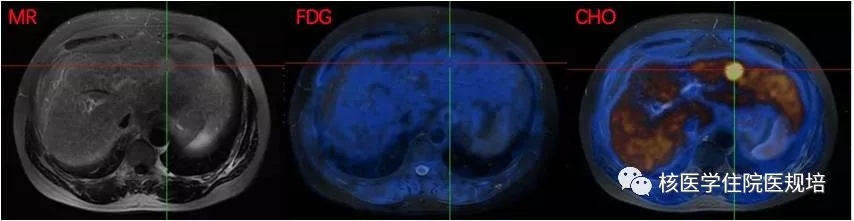

图5. 肝脏11C-胆碱PET/MR,胆碱代谢异常增高。

图6.肝S2段结节,FDG代谢不高,胆碱代谢异常增高。

肝S2段见一等T1稍长T2信号结节,约2.8×2.3cm,边界较清,DWI见弥散受限,局部放射性分布浓聚,早期显像SUVmax 11.8,常规显像进一步浓聚,SUVmax 13.3。

肝S2段结节11C-胆碱代谢增高,FDG代谢不高,综合考虑高分化肝细胞癌可能大。